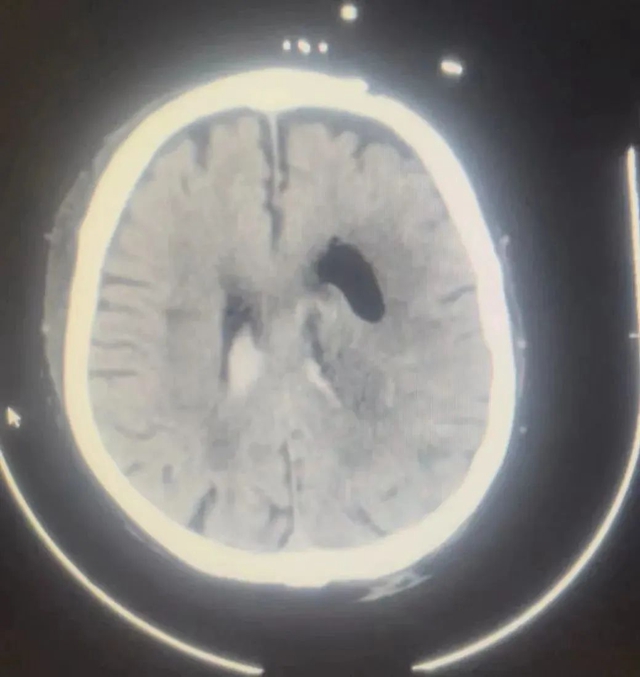

12月11日,余婆婆在家中突发头痛、呕吐,随即出现昏迷,家属赶紧将她送到西南医科大学附属医院(康健中心院区)抢救。急诊CT提示为左侧基底节区高血压性脑出血,出血量高达约60ml,更为不利的是,此时,余婆婆的新冠病毒核酸检测结果显示阳性。

术前术后影像对比

“最有效的处理措施,就是通过清除脑内血肿、降低颅内压。”在陈礼刚教授的统筹协调下,神经外科积极完善术前准备。12月11日,在主刀医生(李慎杰、田俊杰)、手术室医护人员(李青青、莫舻)、麻醉科医生(刘清湄、代俊超)的密切配合下为患者完成了急诊微创颅内血肿清除手术。术后复查颅内血肿清除满意,术后次日患者就已苏醒,并能单独完成睁眼闭眼、抬手、握手、牵铺盖等动作。